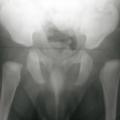

Ostéochondrite de hanche gauche

OSTEOCHONDRITE